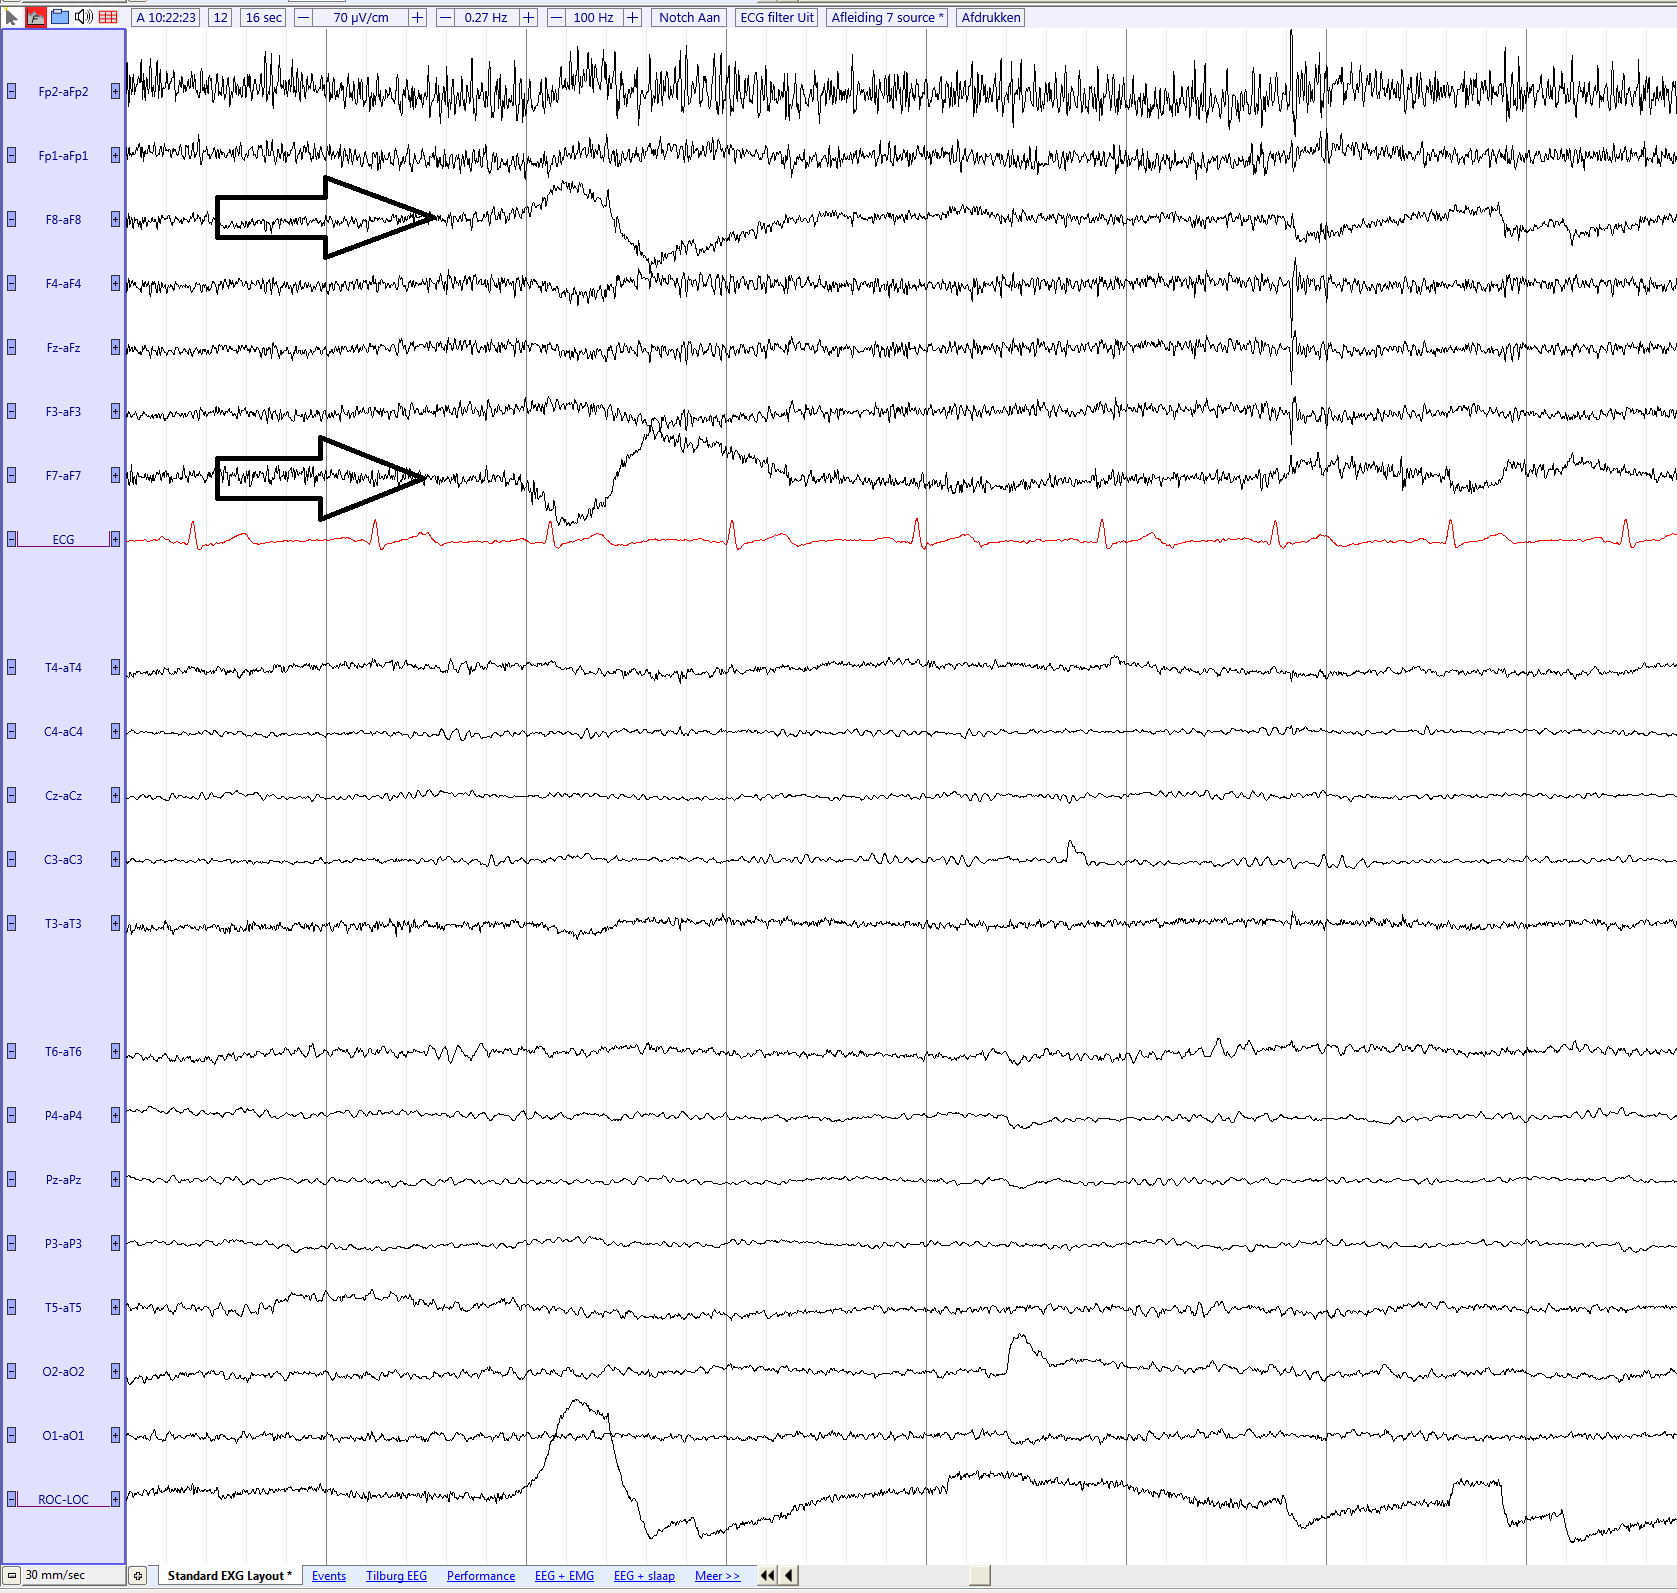

Lateral eye movement seen in F7 and F8

| current | 16:33, 16 May 2017 | 1,677 × 1,593 (142 KB) | EEGpedia (Talk | contribs) | Lateral eye movement seen in F7 and F8 |